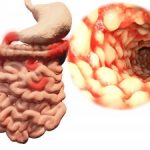

Crohn’s disease, ulcerative colitis progression and development linked to “creeping fat”: Study

Crohn’s disease, ulcerative colitis progression and development linked to “creeping fat”: Study

Crohn’s disease and ulcerative colitis progression and development have been found to be linked to “creeping fat.” Researcher Charalabos Pothoulakis said, “A well-appreciated feature of IBD [inflammatory bowel disease], especially longstanding Crohn’s disease, is intra-abdominal fat, also known as ‘creeping fat,’ which wraps around the intestine. However, it’s not clear whether this fat is protective or harmful. Our study offers insight into this phenomenon. We found that intra-abdominal fat cells may normally be programmed to dampen inflammation but, in fact, have acquired a tendency to promote inflammation in IBD.”

The researchers collected mesenteric fat tissues from 11 colitis patients, 11 Crohn’s patients, and 10 non-IBD controls. The researchers then isolated and cultured preadipocytes, cells that differentiate into becoming part pf adipose tissue where fat is stored for energy. They intended to evaluate the effect of the neuropeptide substance P on the expression of cytokines, which are small proteins important for cell signaling.

The researchers found that signaling mediators produced by the intra-abdominal fat cells in the controls were significantly different from those in the IBD patients. This indicates that these cells are actively involved in gut immunity and inflammation, as pointed out in the press release.

Increased expression of neurokinin-1 and neurokinin-2 receptor mRNA was observed in IBD preadipocytes – compared to controls, while increased expression of substance P mRNA was observed in ulcerative colitis preadipocytes – compared to Crohn’s patients and controls.

The researchers wrote, “Fat represents a novel reserve of IL-17 during the disease and may affect the progress of IBD by altering intestinal responses via interactions with IL-17RA. This observation along with the identification of IL-17 as the most consistently regulated mediator in human mesenteric preadipocytes isolated from IBD patients in response to [substance P] suggests a potential role for this neuropeptide in the regulation of inflammatory changes in the intestine during IBD (both ulcerative colitis and Crohn’s disease) via modulation of IL-17 expression in the adjacent mesenteric preadipocytes. Furthermore, our observations introduce the preadipocytes as a novel cellular population with immune properties that are likely involved in the regulation of intestinal inflammation during IBD.” Continue reading…